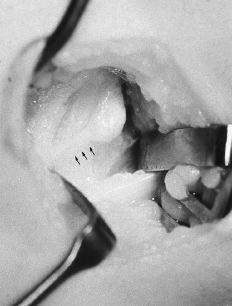

Mediante un acceso medial se alcanzó a la zona por el lado posteromedial del músculo bíceps. Se pudo observar la presencia de una prominencia ósea con un refuerzo fibroso que se dirigía desde la punta de la misma hacia la epitróclea, correspondiendo al denominado ligamento de Struthers (Fig. 2); algunas fibras musculares del pronador redondo se insertaban en la zona más distal de la apófisis. Tras la exposición de la apófisis se apreció su forma de gancho, con una base amplia y de unos 2 cm de longitud, situada en la cara anteromedial del húmero, que se dirigía hacia abajo, adelante y medialmente. En contacto con su cara interna (cubital) se distinguía el nervio mediano y, más medialmente, la arteria humeral, sin que ninguna de estas estructuras presentara alteraciones. No se evidenció ninguna estructura neurovascular en la zona lateral (radial) de la apófisis. Tras la disección anatómica, nerviosa y vascular se procedió a la resección de la exóstosis mediante escoplo, tallando un cajeado de la base de implantación en el húmero (Fig. 3). El período postoperatorio transcurrió sin alteraciones y a los 12 días se retiró el vendaje y los puntos. En la revisión a los 6 meses la paciente estaba asintomática y sin evidenciar signos de recidiva en la radiografía.

Figura 3. Imagen quirúrgica. Se observa la ausencia de estructuras neurovasculares anterolaterales a la apófisis.